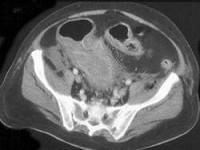

问题 男,18岁,患者皮肤挫伤,用林可霉素预防感染,次日大便次数增多、出现粘液便,结合图像应考虑为 ( )

选项 A.结肠淋巴瘤 B.假膜性肠炎 C.结肠间质瘤 D.结肠结核 E.结肠癌

答案 B